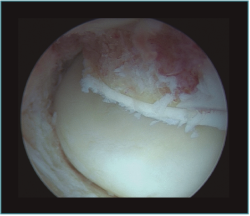

La capsulotomía anterior la iniciaremos de medial a lateral, aproximadamente un centímetro proximal a la punta de la coronoides, utilizando un vaporizador "de gancho" (instrumento que nos parece muy útil para esta tarea, ya que nos permite controlar muy bien la profundidad de la resección de la cápsula para evitar lesionar estructuras neurovasculares próximas); también utilizamos la pinza Basket para resecar la cápsula, sobre todo en los casos en los que está muy engrosada y endurecida (Figura 7). Para disminuir el riesgo de lesión del nervio interóseo posterior (que queda cerca de la cápsula anterior al nivel de la cabeza del radio), dejamos intacta o parcialmente resecada la cápsula sobre la cabeza radial y completamos la capsulotomía con una extensión forzada del codo. Una vez hemos completado la capsulotomía anterior, veremos el tejido muscular del músculo braquial (Figura 8). En este momento no es recomendable resecar más hueso o tejidos blandos por diferentes motivos: al no tener la protección de la cápsula anterior, las estructuras vasculonerviosas están en mayor riesgo de lesionarse; además, en los casos de rigidez el músculo braquial puede ser más delgado, debido a atrofia muscular(14). Otro motivo es evitar el sangrado del músculo, para disminuir el riesgo de aparición de calcificaciones heterotópicas. En caso de ser necesario resecar hueso tras la capsulotomía, emplearíamos un separador a través de un portal anterolateral accesorio y el sinoviotomo o la fresa sin aspirador conectado (Vídeo, minutos 1:36-2:46).

Figura 7. Visión artroscópica desde el portal anteromedial de la realización de una capsulotomía anterior del codo. Vemos la cabeza del radio en la parte más lateral y el músculo braquial en la parte más medial. Apreciamos el grosor de la cápsula anterior en este caso de rigidez postraumática.